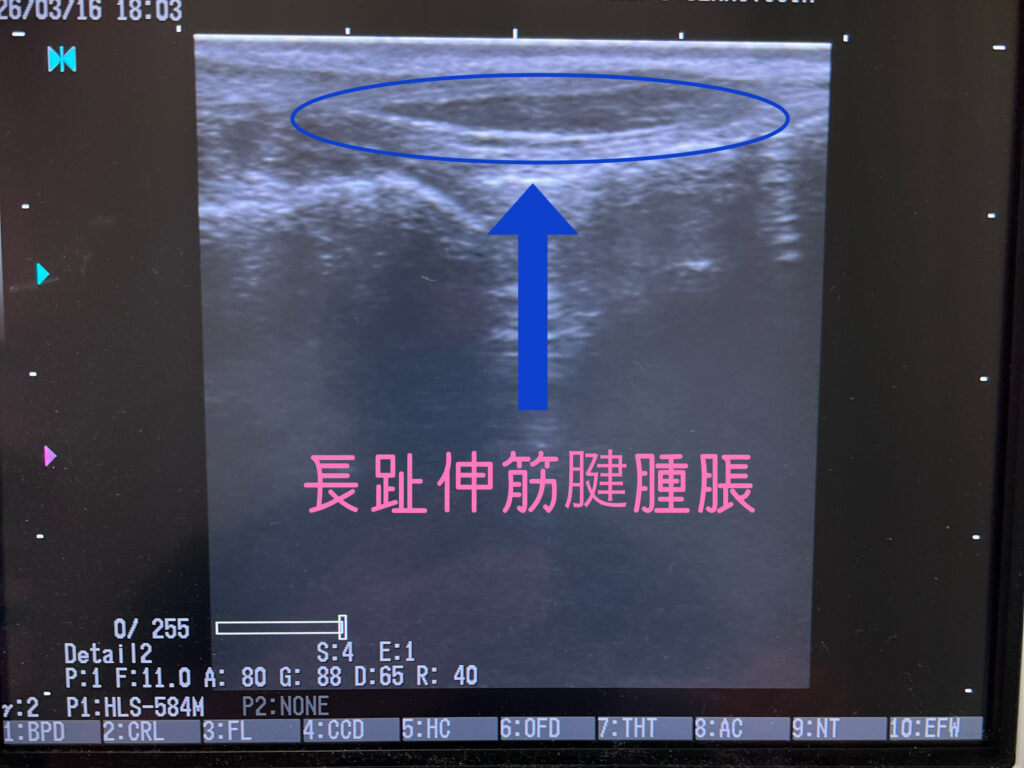

今回もエコー検査でしっかり、長趾伸筋腱自体が腫れているのを確認でき、